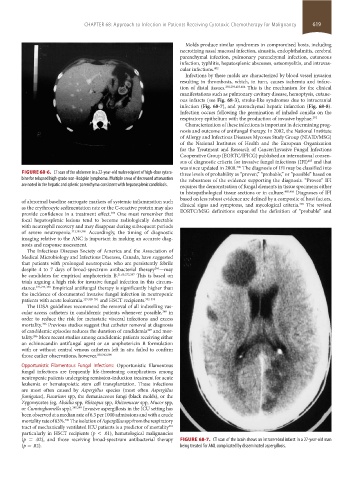

(p = .02), and those receiving broad-spectrum antibacterial therapy FIGURE 68-7. CT scan of the brain shows an intracerebral infarct in a 27-year-old man

(p = .02). being treated for AML complicated by disseminated aspergillosis.